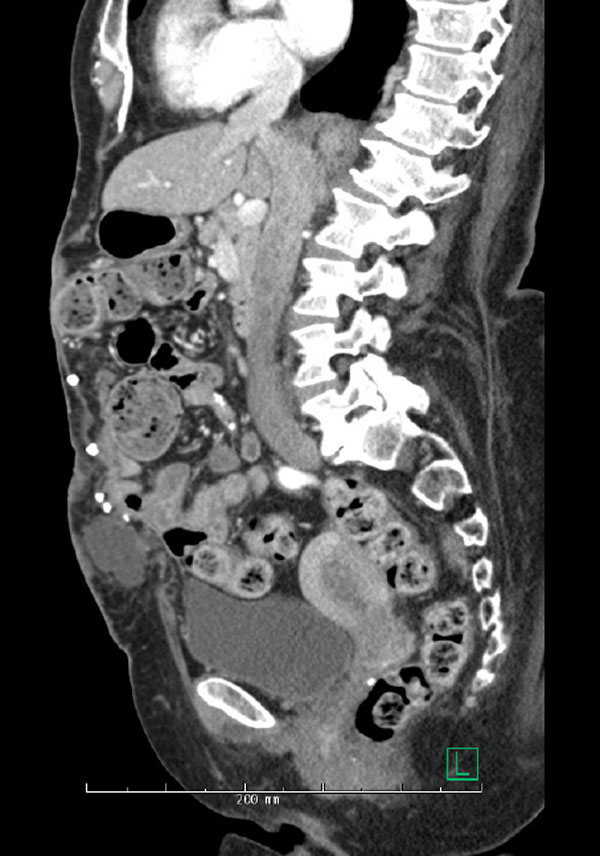

On imaging, she had a 12 x 20 cm area with evidence of multiple old pieces of mesh, metal tacks and a fluid collection in close proximity to the draining wound, which was concerning for a mesh fistula.

Hernia with fluid collection and tacks